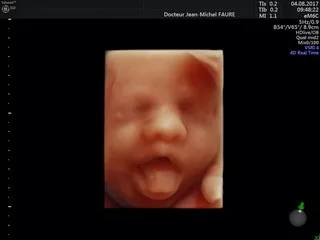

Jean-Michel FAURE

Dr Faure

Tous les examens échographiques sont réalisés avec les échographes les plus récents du marché, mis à jour régulièrement, et sont conformes aux recommandations de bonnes pratiques des sociétés françaises :